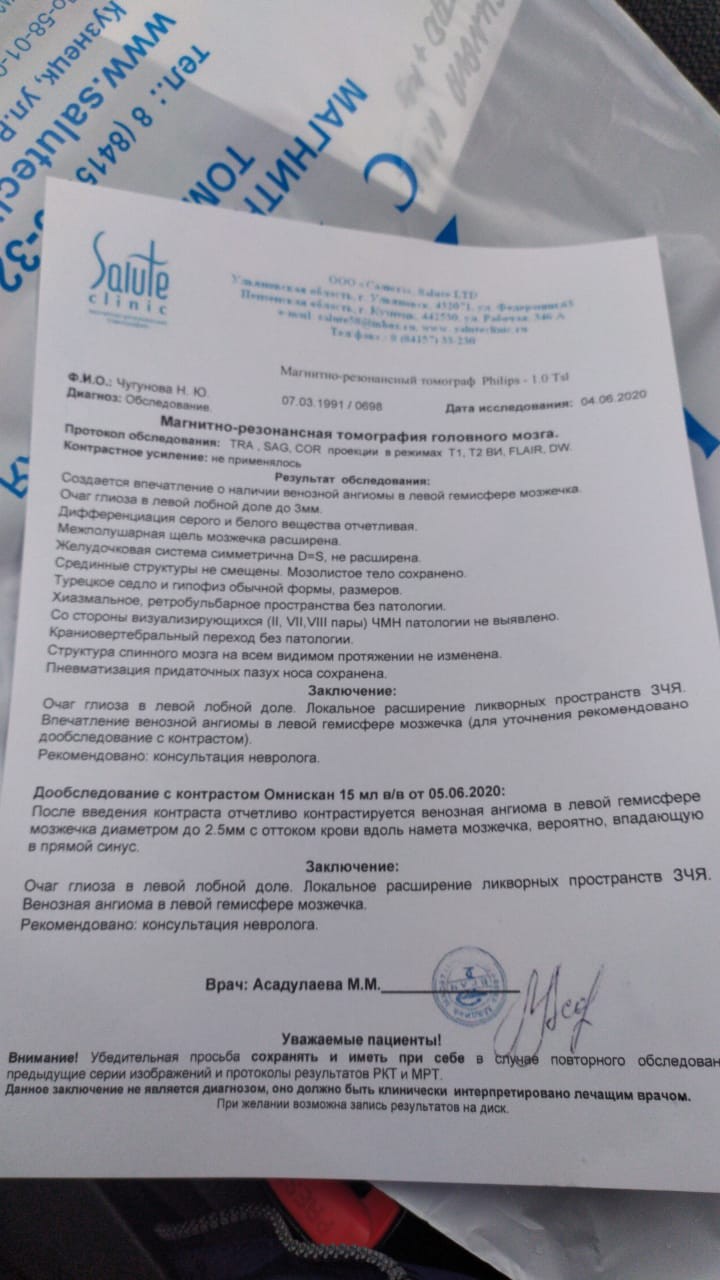

Мр картина венозной ангиомы левой гемисферы мозжечка - 96 фото

Обновлено: 08.06.2025 - 15 фото